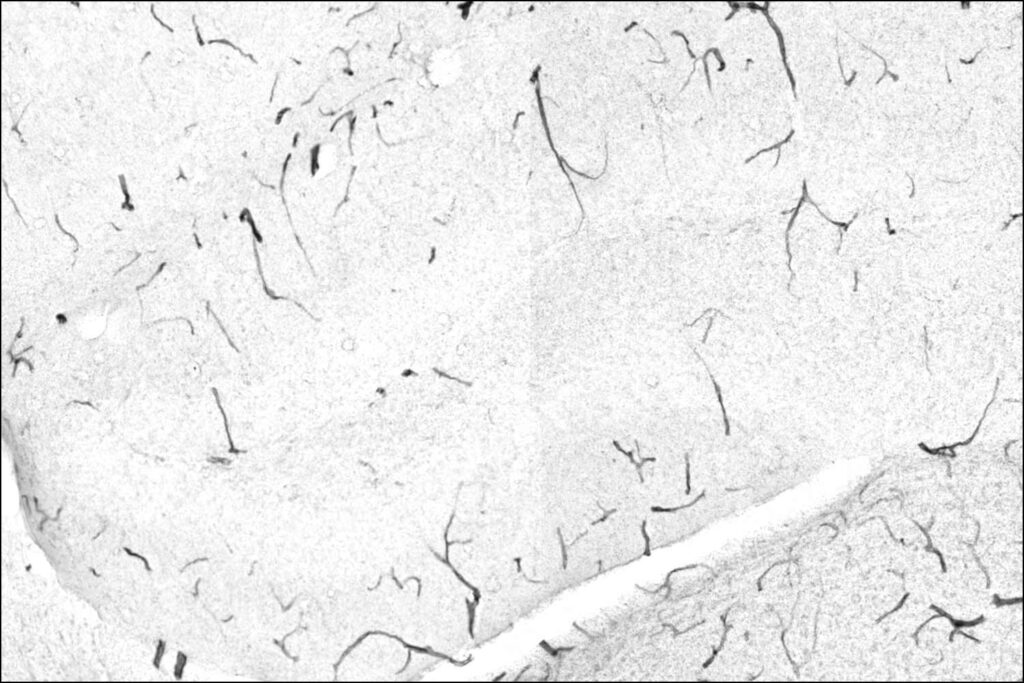

In the team’s model, the key downstream player is TNAP, a protein that accumulates on the cells that form the blood-brain barrier as mice age. That buildup, the researchers report, makes the barrier leaky. Exercise changes the equation: liver-produced GPLD1 travels to the vessels surrounding the brain and trims TNAP off the cells, helping “shore up” the barrier.

To track how GPLD1 might be working, the scientists focused on the enzyme’s core role—cutting certain proteins off cell surfaces—and searched for tissues where these targets might accumulate with age. The blood-brain barrier stood out. When the researchers tested several potential targets in lab experiments, they found GPLD1 only cut one of them: TNAP.

What happened in the mice: cognition worsened when TNAP rose—and improved when it fell

The study’s mouse experiments point to TNAP as more than a marker of aging vessels—it appears to be functionally tied to cognition in this model.

UCSF reports that young mice engineered to have more TNAP in the blood-brain barrier lost cognitive abilities as if they were old.

On the flip side, when researchers used genetic tools to reduce TNAP in 2-year-old mice—an age they describe as roughly equivalent to 70 human years—the blood-brain barrier became less leaky, brain inflammation decreased, and the mice performed better on memory tests.